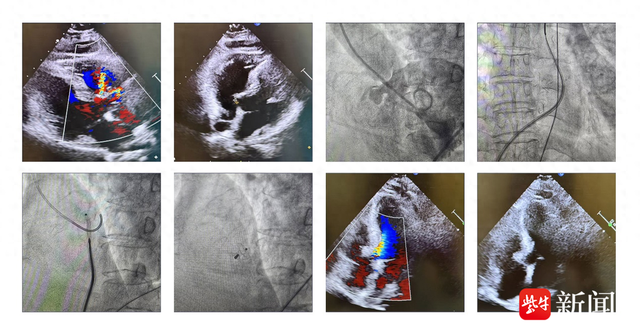

深圳永福医院:女性孕期需要做几次四维彩超?

妇产科医生说,对于许多准父母来说,婴儿的健康是一个持续的问题,所以越来越多的孕妇开始她们在怀孕 期间应该做什么检查。怀孕期间做过多少次四维彩色多普勒超声?针对这些问题,让我们看看深圳永福医 院妇产科医生的介绍。 孕14周左右,孕妇可以做四维彩超检查,检查胎儿的四肢发育情况和一邓工。在这个阶段,四维彩超检查不 会很好地显示胎儿的内脏器官,面部显示的效果也会比较差。 以上问题就是我们对于孕期做几次四维彩超的介绍,对于一个孕妇们而言,应该可以在其孕早、中、晚这 三个发展阶段各进行一次四维彩超检查,对自己的健康教育负责,同时也为自己宝宝的健康管理负责。 深圳永福医院作为深圳市卫计委批准建设的一家集医疗、教学、科研、保健、康复、急救、社区服务于 一体的现代化综合医院,规划建筑面积4万余平方米,床位600张,现已列入深圳市政府卫生规划重点建设项 目,按照三级综合医院标准建设,是深圳市医疗保险、生育保险、健康体检单位。 2、孕22周左右 在此期间做四维彩色多普勒超声可以清楚地了解胎儿面部发育,筛查无脑儿、重度脑膨出和严重脊柱裂 等胎儿发育异常。 3、孕14周左右 1、孕28周左右 孕妇在这段时间做四维彩超检查就可以更加清晰 ...